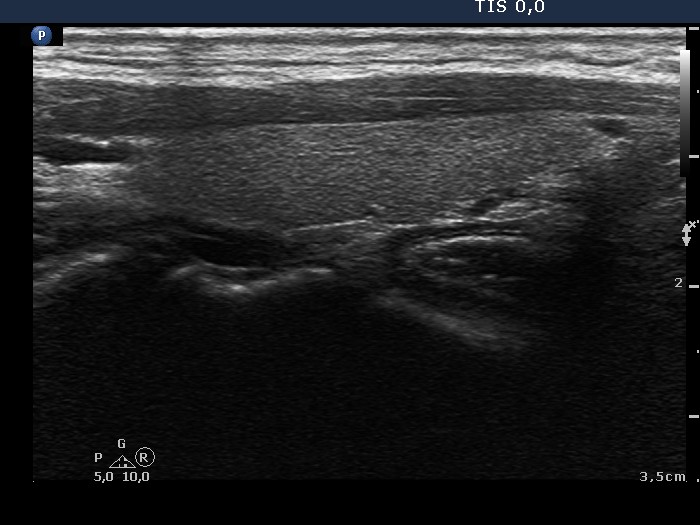

Thyroid cancers - case conp 020 (ultrasonographic picture 4)

Left lobe, longitudinal scan. This lobe is intact.